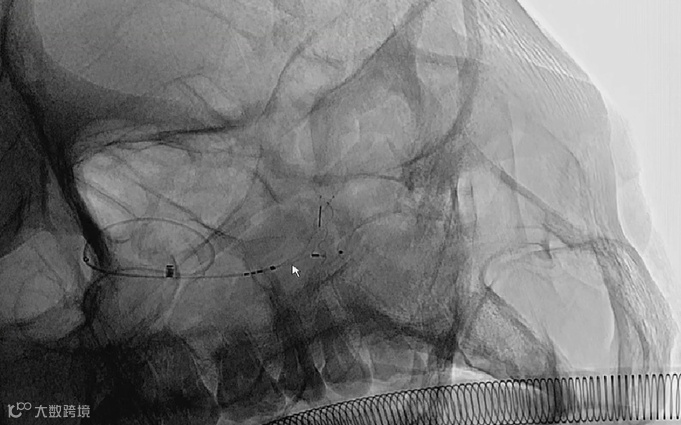

缓慢推送 WEB™至种子-萌芽状态后, WEB™顺着瘤壁慢慢滑向瘤中,缓慢释放 WEB™至开花再到完全释放状态。

WEB™ SL5×3mm释放完成后,输送支架到达动脉瘤远端开始释放。

全部释放完成后,造影显示,分支血管及载瘤动脉血流通畅。

透视下对 WEB™装置进行解脱,解脱后,拉回输送杆,并小心地将 VIA™微导管拉回并确保 WEB™的近端显影点不会被VIA微导管头端卡住。

解脱后,多角度复查造影,可见动脉瘤瘤腔内有明显造影剂滞留,分支血管及载瘤动脉血流通畅。